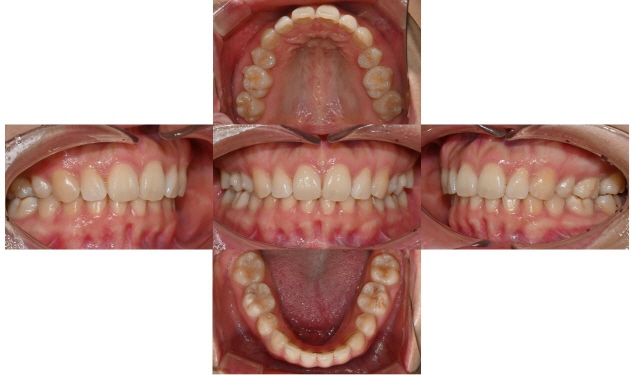

2025.3.5 초진

본 환자는 예전에 발치교정을 했는데 과개교합 때문에 위 치아 유지장치 관리가 잘 되지 않아 앞니가 살짝 벌어지고 치아 하나가 튀어나온 것이 신경이 쓰인다는 주소로 병원에 내원하셨습니다. 과개교합 때문에 위아래 앞니가 서로 부딪혀서 유지장치가 떨어졌고, 유지장치 관리가 잘 안되니 앞니 사이가 점점 벌어지고 오른쪽 앞니가 튀어나온다고 하셨습니다.

장치 교정을 할 경우 사회생활을 하는데 비심미적이고, 기간이 오래 걸려서 빠른 시일 안에 교정 치료를 원하셔서 위 앞니만 인비절라인 익스프레스로 진행하길 원하셨습니다.